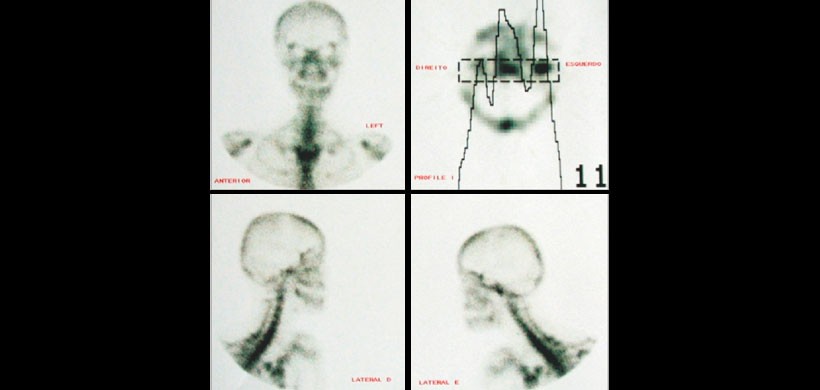

Gammagrafía ósea planar: es un examen que detecta áreas de aumento o disminución del metabolismo óseo. El examen se realiza para identificar procesos anormales que comprometen el hueso, tales como alteraciones en el crecimiento, tumores, infección o fracturas.

Figura 4: Gammagrafía (Scintigrafía ósea) mostrando mostrándo la actividad en el cóndilo mandibular izquierdo.